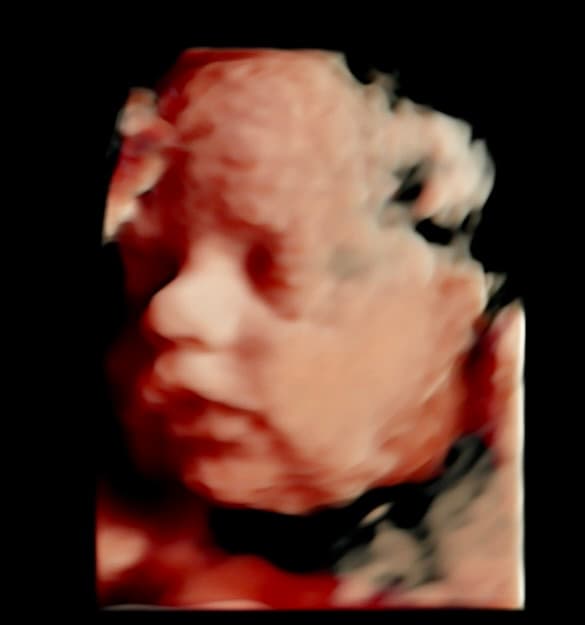

Book NowTahlequah's first 3D/4D ultrasound studio

At Magnolia Fetal Imaging, we provide a warm, relaxing environment where you can bond with your baby through advanced 3D/4D & HD ultrasound technology. Our studio focuses on capturing precious keepsake moments for families — gender reveals, early looks, and high‑definition images you will cherish for a lifetime.

All sessions are non‑diagnostic and designed purely for bonding and keepsake entertainment.